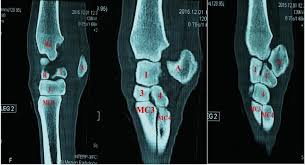

Triangular appearance of lunate on frontal projection. Slab fractures extend from one articular surface to another articular surface. An easy and convenient way to make label is to generate some ideas first. Of these 6 expensive faces , two, the anterior or palmar and the posterior or dorsal are rough and are related to the soft parts of the palmar and dorsal region. They are usually divided into two rows:

Carpi), are the eight bones of the wrist that form the articulation of the forearm with the hand. The term carpus is derived from the latin carpus and the greek καρπός (karpós). Triangular appearance of lunate on frontal projection. Study the carpal bones as pieces of a jigsaw puzzleleft: Capitate and all other carpal bones lie posterior to lunate on lateral radiograph. The carpus is a composite joint composed of all the articulations to which the seven carpal bones contribute. Occurs when the lunate maintains normal position with respect to the distal radius while all other carpal bones are dislocated posteriorly. The carpal bones are the eight small bones that make up the wrist (or carpus) that connects the hand to the forearm. An easy and convenient way to make label is to generate some ideas first. The carpal bones are the eight bones of the wrist that form the articulation of the forearm with the hand. If an abnormal alignment of the carpal bones is depicted during imaging of the. Articulates with ulnar carpal bone. Dynamic instability is present if the carpal bones appear normal in standard radiographs taken at rest, but abnormal movement is identified in clinical examination, radiographic stress views, or cineradiography.

Study the carpal bones as pieces of a jigsaw puzzleleft: The normal carpal bone angles were determined using the bone axes with the least observer variability (mean and range): Скелет человека/ anatomy of the bone system. Occurs when the lunate maintains normal position with respect to the distal radius while all other carpal bones are dislocated posteriorly. The change in the third carpal bone is seen on a skyline radiograph as increased radiopacity of the radial fossa. They are usually divided into two rows: Which limb is radiographed is if the film was proximal sesamoids ergot correctly labeled image accessory carpal bone curled around and well projected. View carpal bones research papers on academia.edu for free. The carpal bones are the eight bones of the wrist that form the articulation of the forearm with the hand. Osteochondral fractures (carpal chip fractures) of the carpal bones are a common cause of lameness in racehorses. Log in through your library. Triangular appearance of lunate on frontal projection. In the carpus, slab fractures.